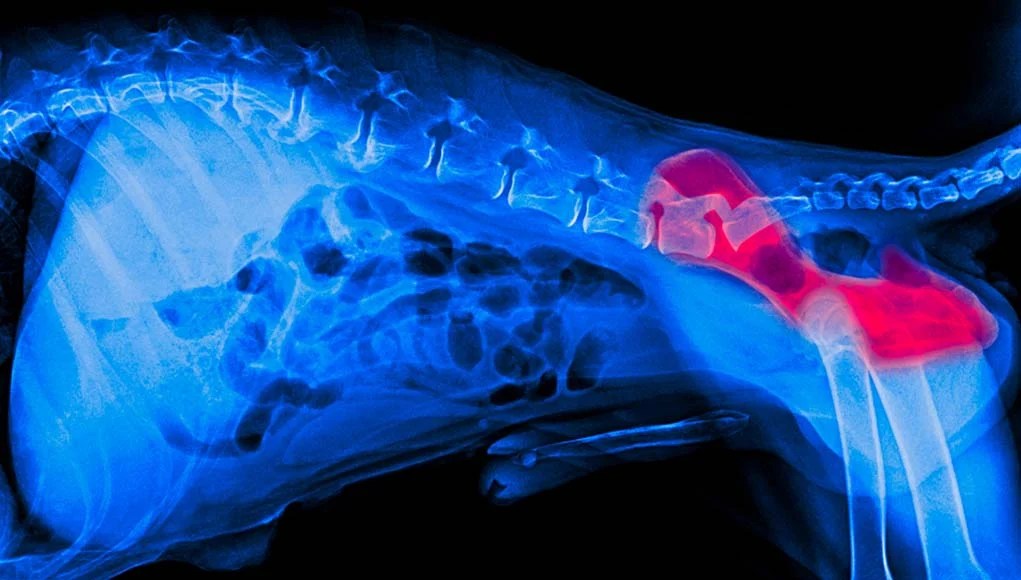

Signs Of Hip Problems In Dogs. it’s crucial for pet parents to recognize the signs of hip pain in dogs in order to provide timely care. A hip radiograph under general anesthetic is the preferred method for diagnosing hip dysplasia. In this article, you will learn what causes hip pain in dogs, signs of hip pain to recognize, when to seek help from your veterinarian, and how you can help your dog with hip pain at home. 5 warning signs of hip dysplasia in dogs. Most of the symptoms of dogs' hip problems can be spotted easily and quickly because. how is it diagnosed? hip dysplasia is a common inherited disease in dogs. November 21, 2023 dogs, pets. the symptoms of chd are lameness (limping), reluctance to rise or jump, shifting of weight to the forelimbs, loss of muscle mass on the rear limbs,. in this article, we’ll go through common hip conditions you might see in your dog so you understand the signs, preventative measures, and. signs of hip problems in dogs. As a dog owner, you want to make sure your. It can be very painful and can cause other conditions,.

Most of the symptoms of dogs' hip problems can be spotted easily and quickly because. it’s crucial for pet parents to recognize the signs of hip pain in dogs in order to provide timely care. As a dog owner, you want to make sure your. signs of hip problems in dogs. A hip radiograph under general anesthetic is the preferred method for diagnosing hip dysplasia. In this article, you will learn what causes hip pain in dogs, signs of hip pain to recognize, when to seek help from your veterinarian, and how you can help your dog with hip pain at home. November 21, 2023 dogs, pets. the symptoms of chd are lameness (limping), reluctance to rise or jump, shifting of weight to the forelimbs, loss of muscle mass on the rear limbs,. 5 warning signs of hip dysplasia in dogs. how is it diagnosed?

Signs Of Hip Problems In Dogs how is it diagnosed? Most of the symptoms of dogs' hip problems can be spotted easily and quickly because. November 21, 2023 dogs, pets. how is it diagnosed? It can be very painful and can cause other conditions,. the symptoms of chd are lameness (limping), reluctance to rise or jump, shifting of weight to the forelimbs, loss of muscle mass on the rear limbs,. A hip radiograph under general anesthetic is the preferred method for diagnosing hip dysplasia. in this article, we’ll go through common hip conditions you might see in your dog so you understand the signs, preventative measures, and. In this article, you will learn what causes hip pain in dogs, signs of hip pain to recognize, when to seek help from your veterinarian, and how you can help your dog with hip pain at home. signs of hip problems in dogs. As a dog owner, you want to make sure your. it’s crucial for pet parents to recognize the signs of hip pain in dogs in order to provide timely care. hip dysplasia is a common inherited disease in dogs. 5 warning signs of hip dysplasia in dogs.